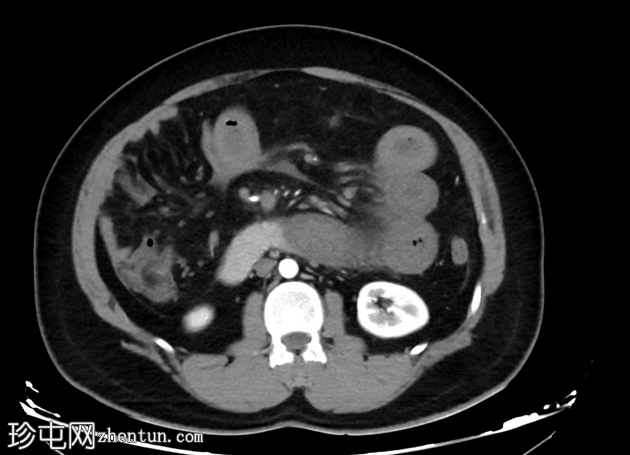

轴向C+动脉期

肠系膜上静脉及其主要支流广泛血栓形成,延伸至脾静脉和门静脉,包括门静脉右支和近端左支。

小肠管增厚、水肿、低灌注,提示小肠缺血。

由于门静脉右支血栓形成,肝右叶低灌注,导致短暂性肝密度差(THAD)。

胃部膨胀,充满液体。

腹部少量游离液体。